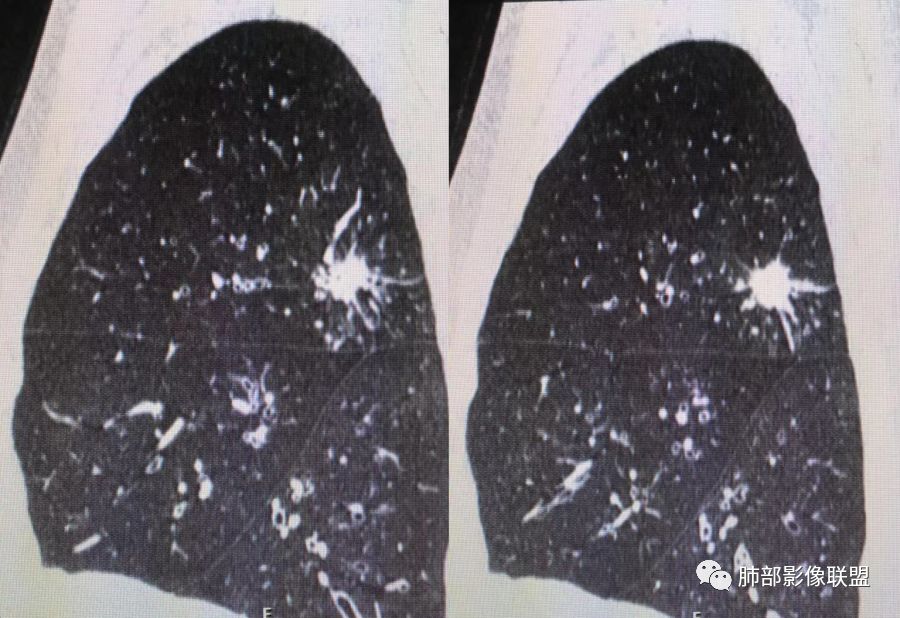

胸CT示病变位于右肺上叶,右肺上叶前段支气管壁不规则增厚狭窄、远端扩张。右肺上叶后段实变影,纵隔窗实变内可见钙化灶,可见支气管引流征,引流支气管壁明显增厚,边缘可见短硬毛刺,胸膜牵拉,u型征,周围可见卫星灶,并可见支气管扩张及其管壁增厚;病灶整体存在膨胀性生长。考虑良性病(结核)变基础上合并癌变,腺癌?

患者中老年男性,咳嗽喘息半年。查体双肺闻及哮鸣音。胸部CT:右肺上叶后段不规则结节灶,可见长毛刺、胸膜牵拉、分叶及钙化征象,周围见点片状卫星灶,近端支气管壁增厚,呈支气管爬行征。综合考虑结核。鉴别恶性病变。

右上肺的占位,毛刺,凹陷,总体偏恶性,但周围卫星灶,考虑腺癌可能性最大,结核也不能排除。

老年男性,咳嗽半年,右肺上叶后段实性结节伴粟粒状卫星灶,结节内有钙化,部分边缘平直,周围见长索条,有胸膜牵拉,结核是明确的,常规需要增强判断有无合并肺癌,当然该患者已经穿刺。

右肺上叶后段结节,点状钙化,边缘见细长毛刺,胸膜凹陷,卫星灶伴树芽症,支气管壁增厚扩张,有截断,考虑结核,但腺癌没法排除,确实有增强就基本能明确。

右肺上叶后段实性结节伴卫星灶,结节内有钙化,部分边缘平直,长索条,胸膜牵拉,考虑结核,但恶性征象还是有的,需除外腺癌!

右肺上叶后段不规则结节,长毛刺,卫星灶,斑点状钙化伴细小钙化,边缘部分平直,收缩力不强,倾向一元解释TB可能大,鉴别腺癌

右肺上叶病灶,可见分叶、毛刺、胸膜牵拉,周围见花花草草,似乎是卫星灶,考虑结核,鉴别腺癌。右肺支气管管壁增厚并扩张,考虑支扩,病史有喘息,哮鸣音,考虑合并有曲霉菌感染。综合考虑腺癌合并结核,曲霉感染。二元。

右肺上叶后段结节,长毛刺、钙化灶、近端小空洞、索条影、周围支气管树丫、引流支气管增厚,主体病灶侧后方分隔样空腔,弥漫支气管增厚,大气道受累,支持感染的征象较多,TB、曲霉;分叶、膨隆、脊状凸起、毛刺等恶性征象也有,遗憾没看到增强,只有期待活检一槌定音。

右肺上叶后段结节,呈不规则状,内可见钙化,边缘可见长短不一毛刺及胸膜牵拉,并可见分叶,邻近支气管管壁增厚,周围可见多发点状及结节状高密度影,首先考虑结核。

老年男性,咳嗽半年,右肺上叶后段实性结节,内见钙化,边缘部分膨隆,有长短毛刺、分叶、空泡征,胸膜侧见胸膜牵拉,周围不干净,见小卫星灶,右上叶后段支气管管壁增厚,扩张,有炎性及恶性征象,一元论常规考虑炎性肉芽肿病变,结核可能,腺癌不除外,二元结核并腺癌,建议增强及穿刺活检。

右上肺后段结节,边界清晰,可见分叶及毛刺,血管集束征,胸膜牵拉,内见斑点状钙化,周围见斑点状模糊影,同时伴支气管扩张,管壁增厚。整体感觉恶性征象多于良性,首先考虑肺癌,鉴别肉芽肿性病变,结核位置不像。

右肺上叶后段占位,毛刺,胸膜凹陷,病灶边缘内可见钙化、空泡,血管进入,病灶周围可见多发粟粒及树芽征,首先考虑肺结核;鉴别腺癌?鳞癌(周围小花、小草?)?

右上叶结节,毛刺、胸膜兔儿、空泡、钙化、血管,恶性征象不少,但是,可见沿支气管血管束分布的,周围可见卫星病灶,支气管扩张,外边胸膜是增厚的,结核可能性大。

中年男性,CT提示右肺上叶后段可见一结节影,可见长、短毛刺,胸膜牵拉,邻近支气管壁增厚,可见卫星灶,病灶内可见钙化,符合结核改变,腺癌待排。

右肺上叶后段团块影,内见钙化,周围胸膜有牵拉,近段支气管扩张管壁增厚,周围可见卫星灶,右支气管狭窄,综合考虑支气管内膜结核,鉴别真菌感染(气道侵袭性曲霉菌病)。

中老年男性,右肺上叶不规则团块状病灶,深分叶、长软毛刺,内部见空泡、多发钙化,相邻支气管增厚,考虑病变来源于气道,首先考虑结核,有空泡,这个腺癌多见,需要鉴别。

右肺上叶后段不规则结节,可见多发长毛刺,边界欠清,密度不均匀,其内可见斑点状钙化影,相应支气管壁增厚,管腔通畅,病灶周围见斑片状、斑点状稍高密度模糊影,考虑结核可能性较大。

中老年男性,右肺上叶不规则团块状病灶,深分叶、长毛刺,内部见空洞(近心侧)、钙化,相邻支气管增厚,有结核背景,首先考虑结核,腺癌需要鉴别。

右肺肿块,边缘平直,往下部分有膨胀感,毛刺、胸膜牵拉,内钙化,周围树芽,边界清,支气管壁增厚,考虑结核;不除外合并恶性。

右上后段结节,整体收缩,长软毛刺丶胸膜凹陷,有点状钙化丶小空洞,引流支气管明显管壁增厚,周边卫星灶明显,有喘息史半年,可能有应用激素史,致内源性复发,考虑TB,鉴别腺癌。

右肺上叶后段占位,分叶,毛刺,胸膜凹陷,病灶边缘内可见钙化、空泡,血管进入,病灶周围卫星灶,考虑肺结核合并肺癌。

不给增强图像,仅就形态判断,腺癌、结核都有可能。腺癌:分叶,毛刺,胸膜牵拉,近端支气管爬行结核:分叶,毛刺,胸膜牵拉,粗颗粒钙化散在分布,引流方向支气管壁增厚。这种情况通常放射科诊断不下结论:部位,病变,建议增强检查/穿刺活检。

3.本例病灶影像表现为:右肺上叶后段不规则结节灶,病灶整体存在膨胀性生长,可见毛刺、胸膜牵拉、分叶及钙化征象,近心端小空洞,周围见点片状卫星灶并出现磨玻璃影,近端支气管壁增厚,管腔扩张,既有恶性征象,也有结核的征象。南边老师考虑结核与腺癌同时存在,但遗憾的是缺乏增强扫描图像,亦未提供结核相关辅助检查结果。